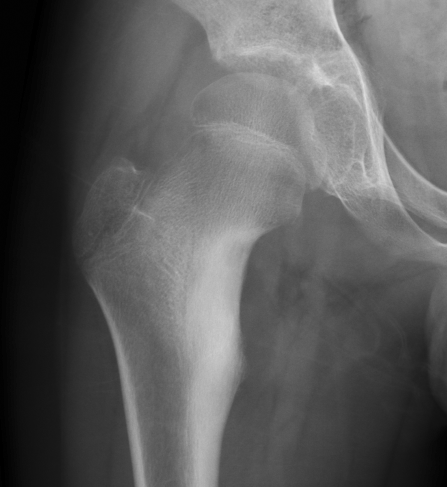

▌膨胀性破坏

膨胀性破坏是地图样破坏的特殊形式,影像学表现为骨质破坏区骨膨胀,周围可见不同程度扩张的骨壳(图 5、图 6、图 7、图 8)。膨胀性破坏是由于肿瘤从骨皮质内面破坏,骨外膜增生形成新生骨造成膨胀的。引起膨胀性破坏见于大多数良性肿瘤和肿瘤样病变如单纯性骨囊肿,动脉瘤样骨囊肿、内生软骨瘤和软骨粘液纤维瘤等,少数也可见于恶性肿瘤如转移瘤、骨髓瘤等。

图 6.膨胀性破坏:骨巨细胞瘤